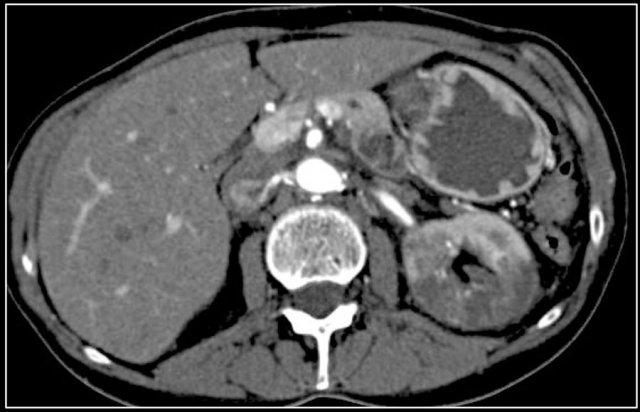

Do đó, thì thận (nephrogenic phase) là thì nhạy cảm nhất để phát hiện các tổn thương này, vì nhu mô thận ngấm thuốc đồng nhất và đậm hơn so với khối u (hình minh họa).

Tổn thương thâm nhiễm ở cực trên thận phải, hầu như không thấy trên ảnh không tiêm thuốc (bên trái), thấy rõ ràng ở thì thận (bên phải). Giải phẫu bệnh xác nhận RCC tế bào sáng

Trong số tất cả các RCC tế bào sáng, khoảng 5% có kiểu tăng trưởng thâm nhiễm.

Mặc dù đây chỉ là một tỷ lệ nhỏ trong số các RCC, nhưng tần suất chung của RCC khiến đây trở thành một chẩn đoán phân biệt quan trọng đối với tổn thương thâm nhiễm dạng hình đậu (bean-type).

RCC thâm nhiễm có tính chất xâm lấn cao và tăng sinh mạch máu.

Tổn thương làm thay đổi cấu trúc nội tại của thận nhưng vẫn bảo tồn đường bờ thận. Các bất thường hệ thống đài bể thận có thể tương tự như những gì thấy trong ung thư biểu mô tế bào chuyển tiếp (transitional cell carcinoma).